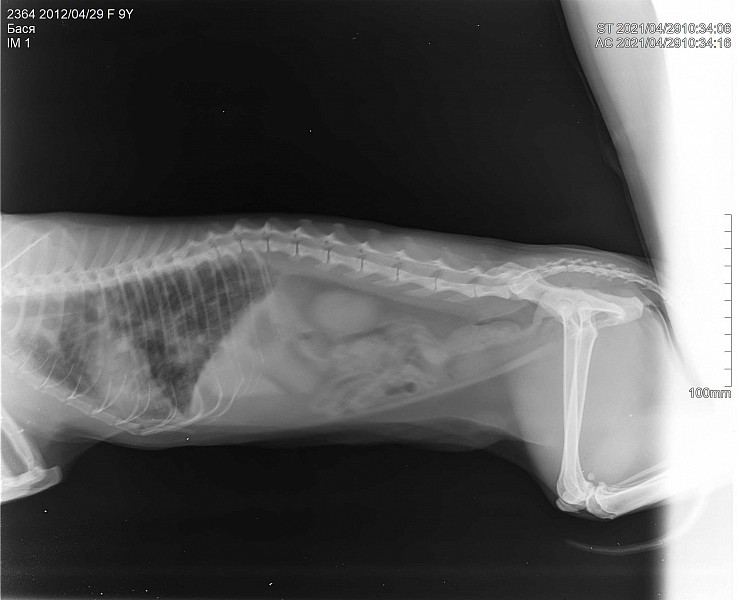

Рак легких либо пневмания у кошки? - 02 мая 2021 - Форум Зоовет